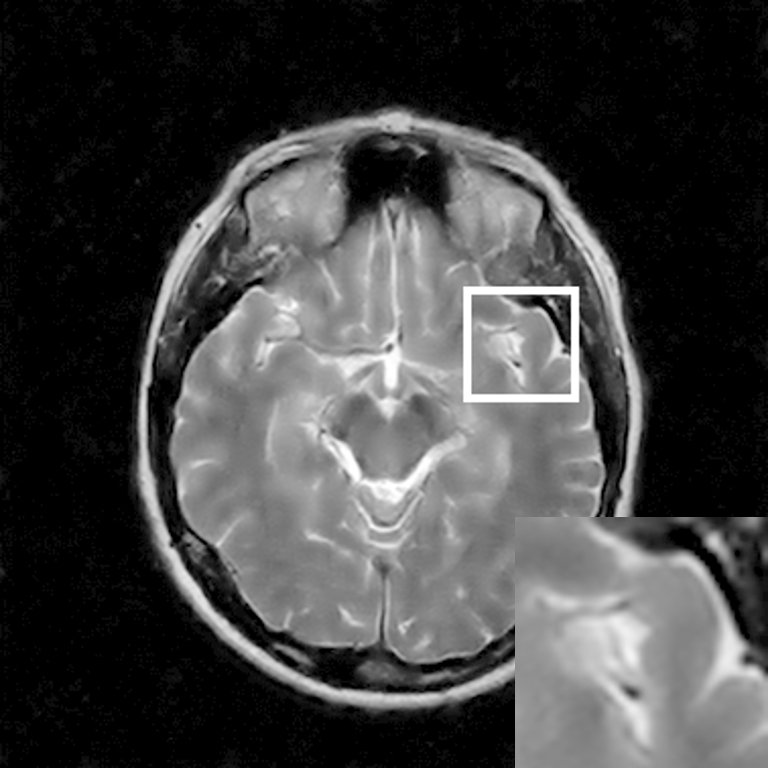

Figure 7: Reconstruction results for 20% variable density sampling. (a) Original. (b)-(h) Reconstructed images. (i)-(n) The errors of six CSMRI methods.

As shown in Figs. 7, 8 and 9, Sparse MRI and DLMRI have a lot of unpleasant artifacts, Residual learning and U-net can eliminate most of artifacts, but are not ideal for restoring image details. However, the proposed method can reconstruct better MR images, which outperforms other competitive methods in visualization of structures reconstruction and artifacts removal. Meanwhile, we can see from the absolute error residuals for three sampling experiments that the proposed MDN algorithm restores a finer detail structure than other algorithms. Moreover, we present the PSNR and SSIM values in Table I for different algorithms, sampling masks and sampling rates. It is demonstrated that the proposed method provides better reconstruction performance and visual results than other competitive methods. We can also see the obvious improvement of all algorithms over zero-filling both in visualization. In particular, a higher SSIM value of Sparse MRI appears when using 30% variable density random sampling, however, Sparse MRI generates more artifacts than the proposed MDN.